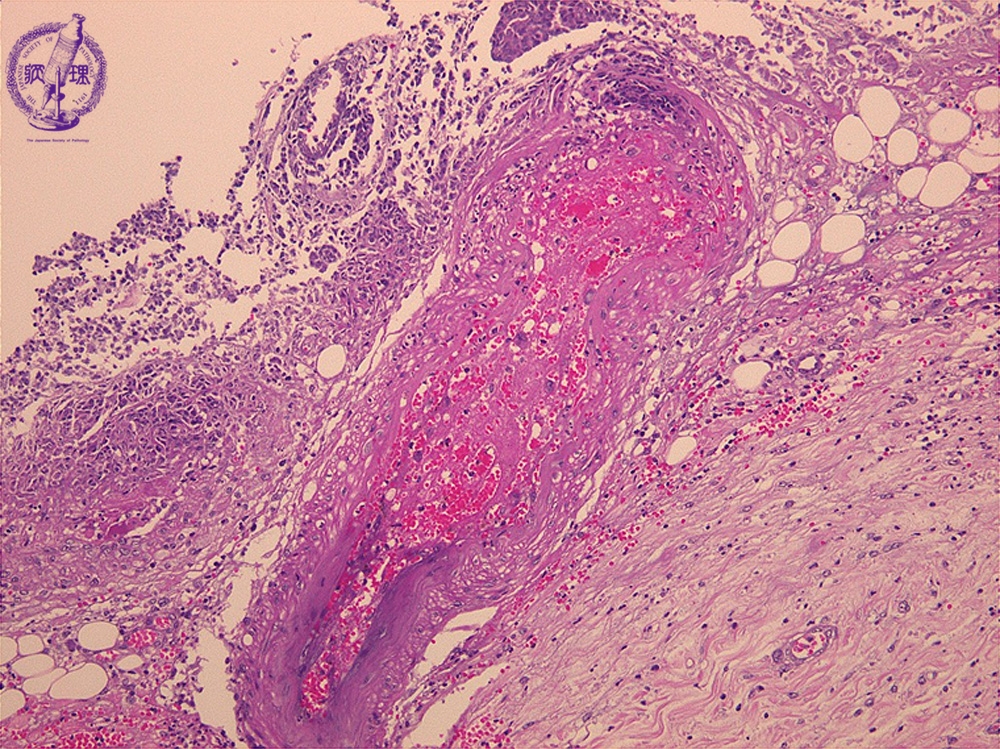

Microscopic view (H&E stain, high power): Blood vessels (blue) within the ulcer bed are necrotic (arrow) and contain post-hemorrhagic organizing thrombus (yellow).

Click the image to see the enlarged image.